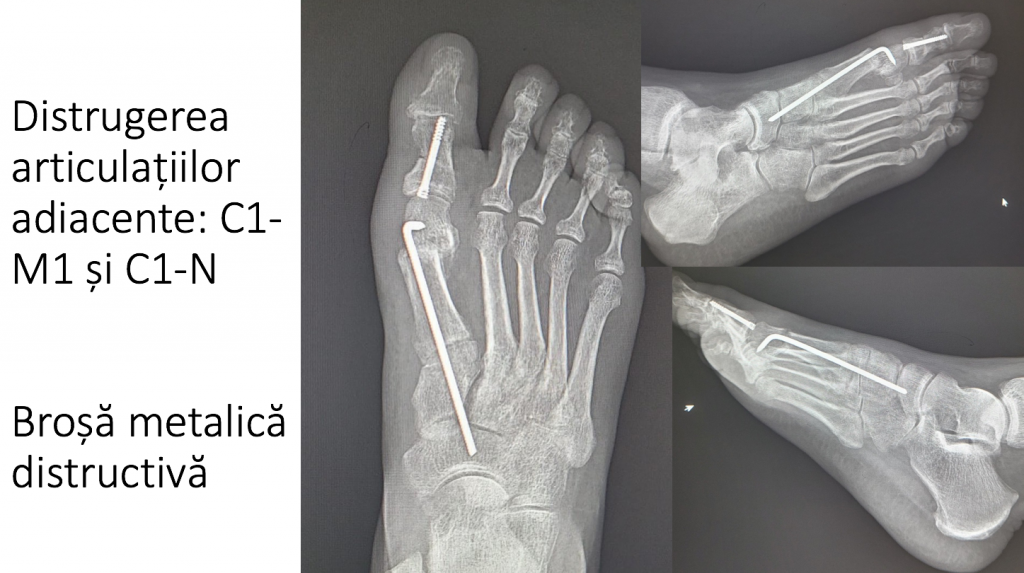

17. DISTRUGEREA ARTICULAȚIILOR ADIACENTE

- materialele de osteosinteza trebuie sa evite articulatiile;

- penetrarea articulatiilor cu brose metalice determina distrugerea rapida a acestora (artroza sau chiar blocarea articulatiilor).